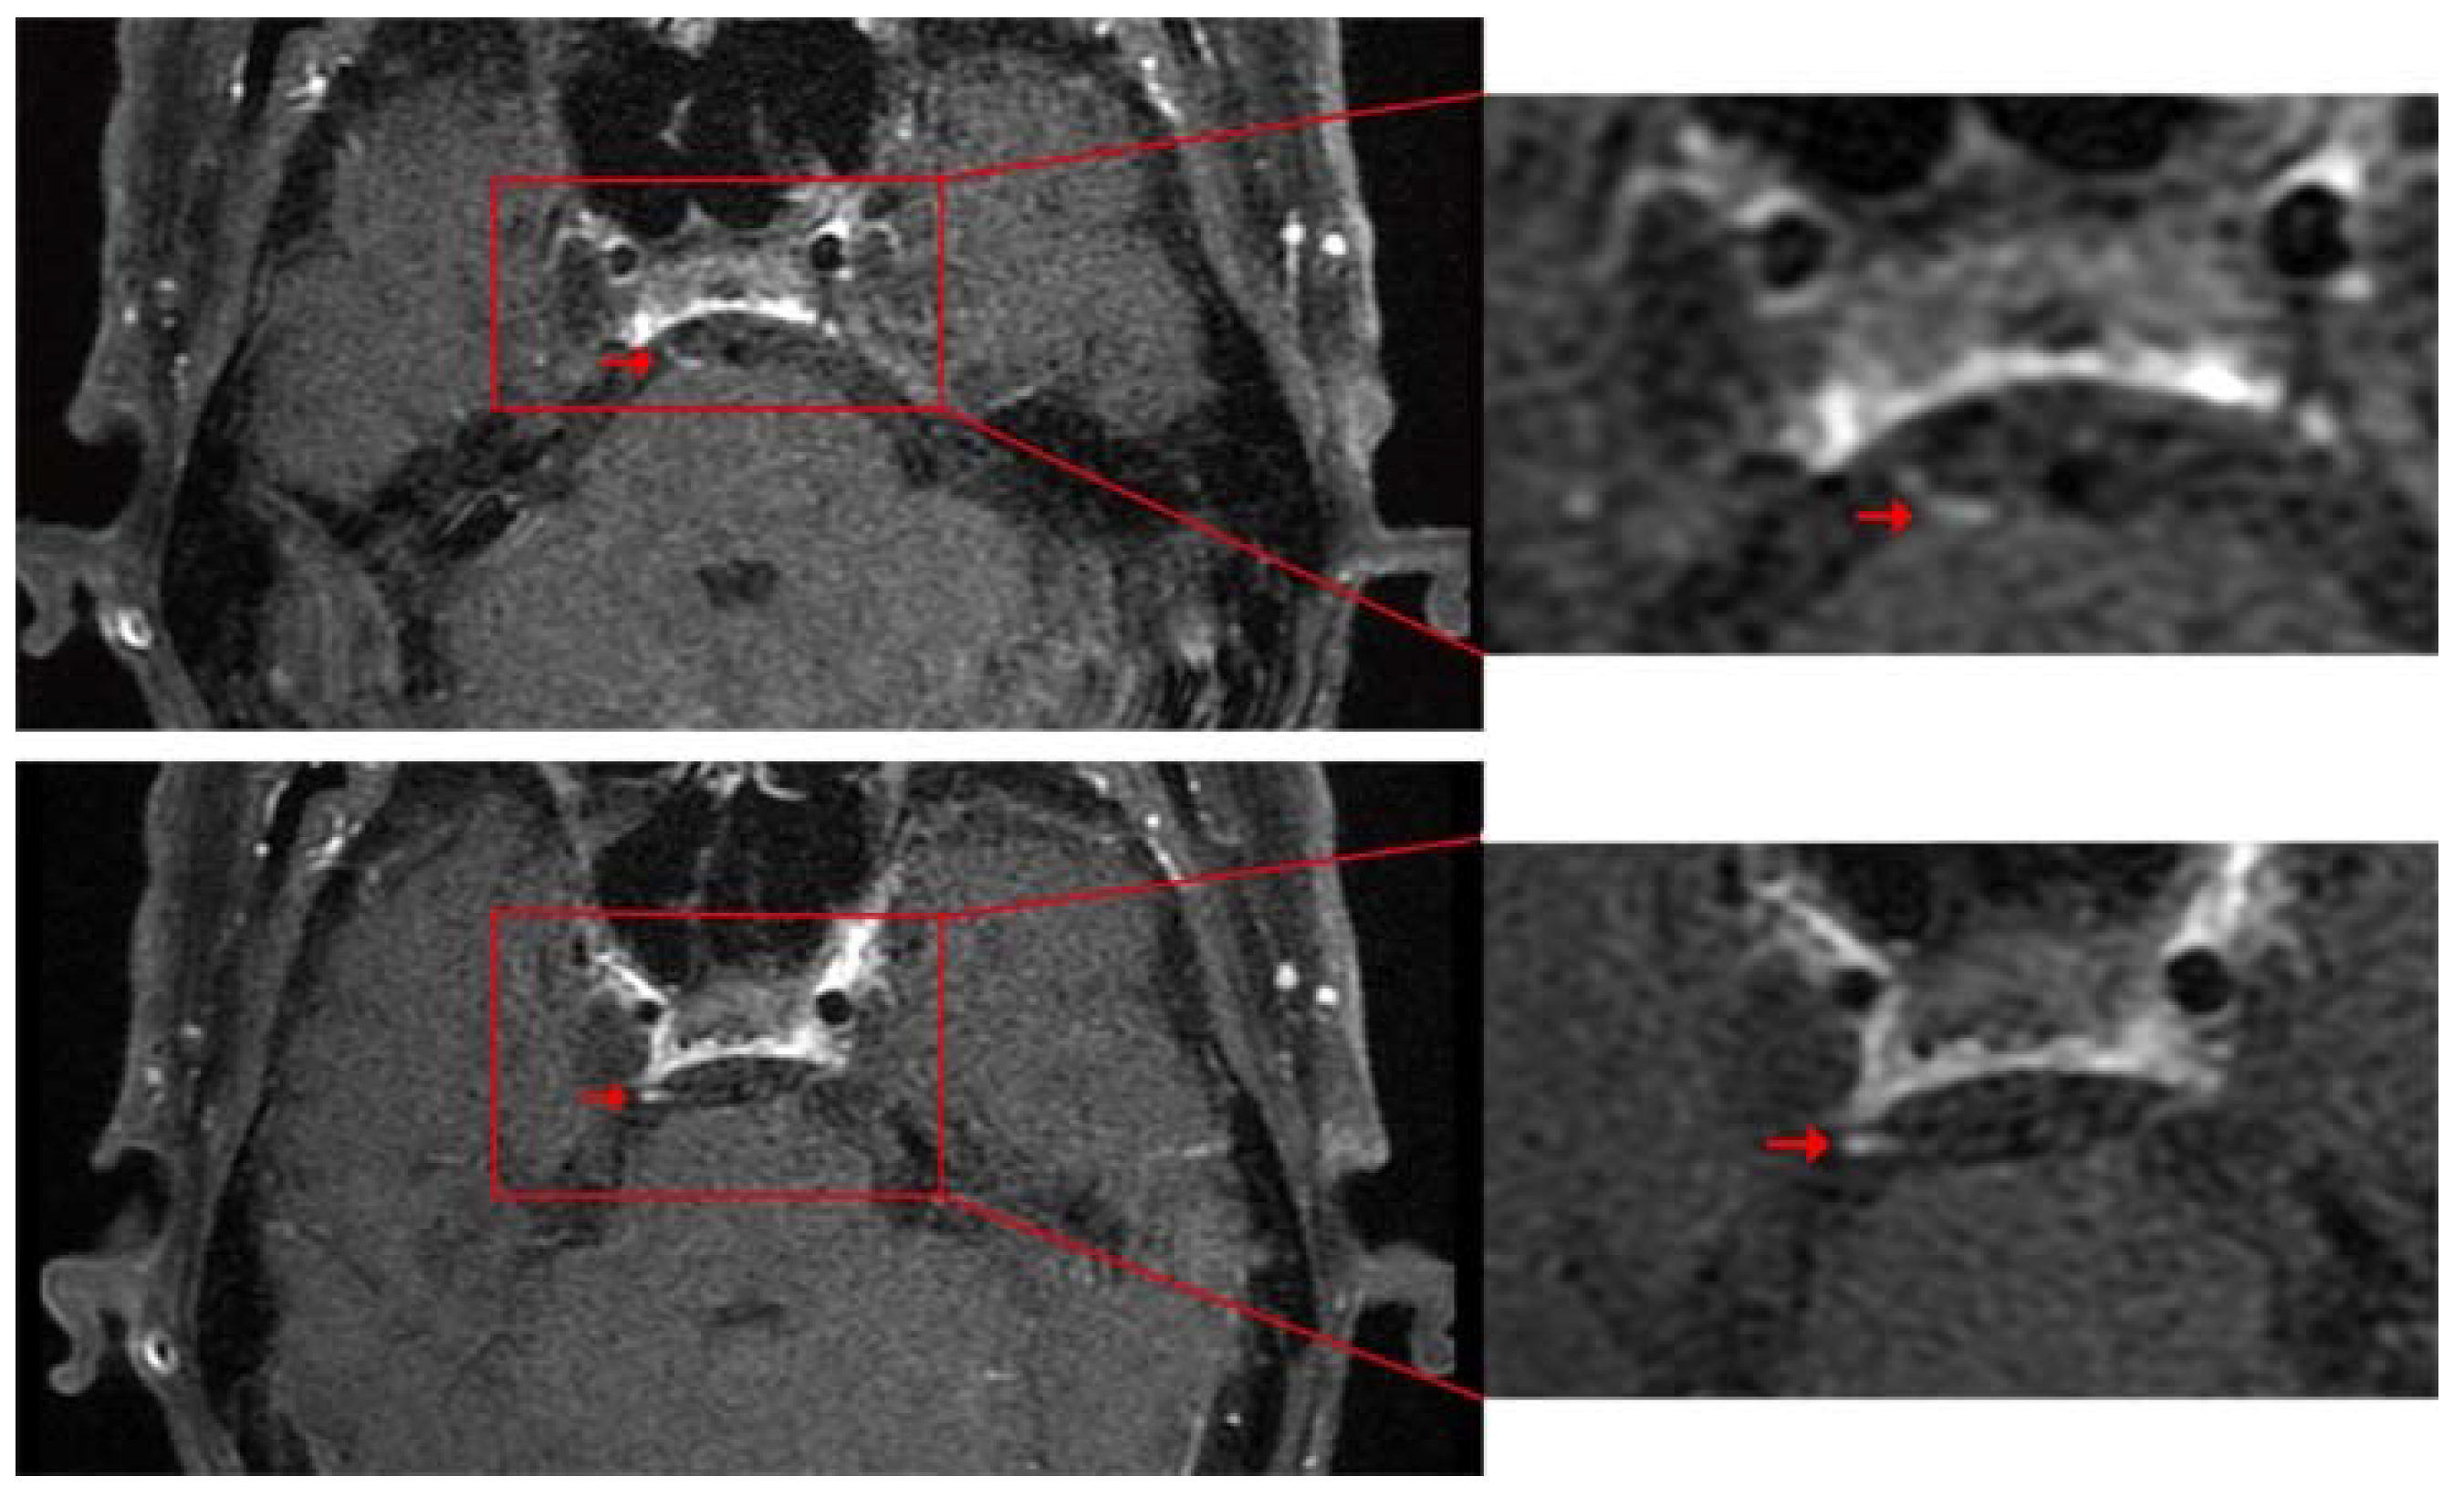

2. Case Presentation